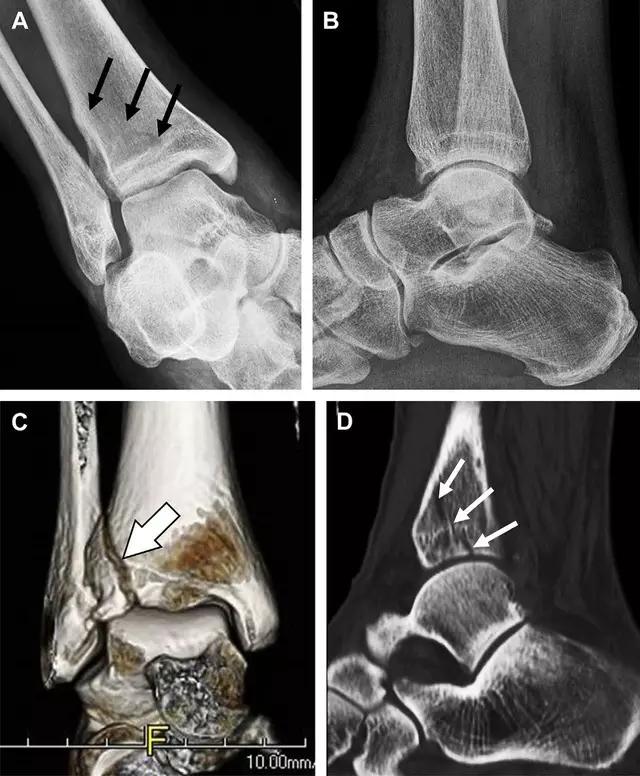

摔倒后胫骨结节骨折。A 正位片示一细小斜型骨折线(箭头);B 侧位片示正常;C 冠状位 CT 三维成像更清晰地显示了骨折线和骨折块大小(空箭头);D 矢状位 CT 多维重建图像示骨折位置(箭头)(来源:Radiol Clin N Am 53 (2015) 737–755,YU,Ohio)